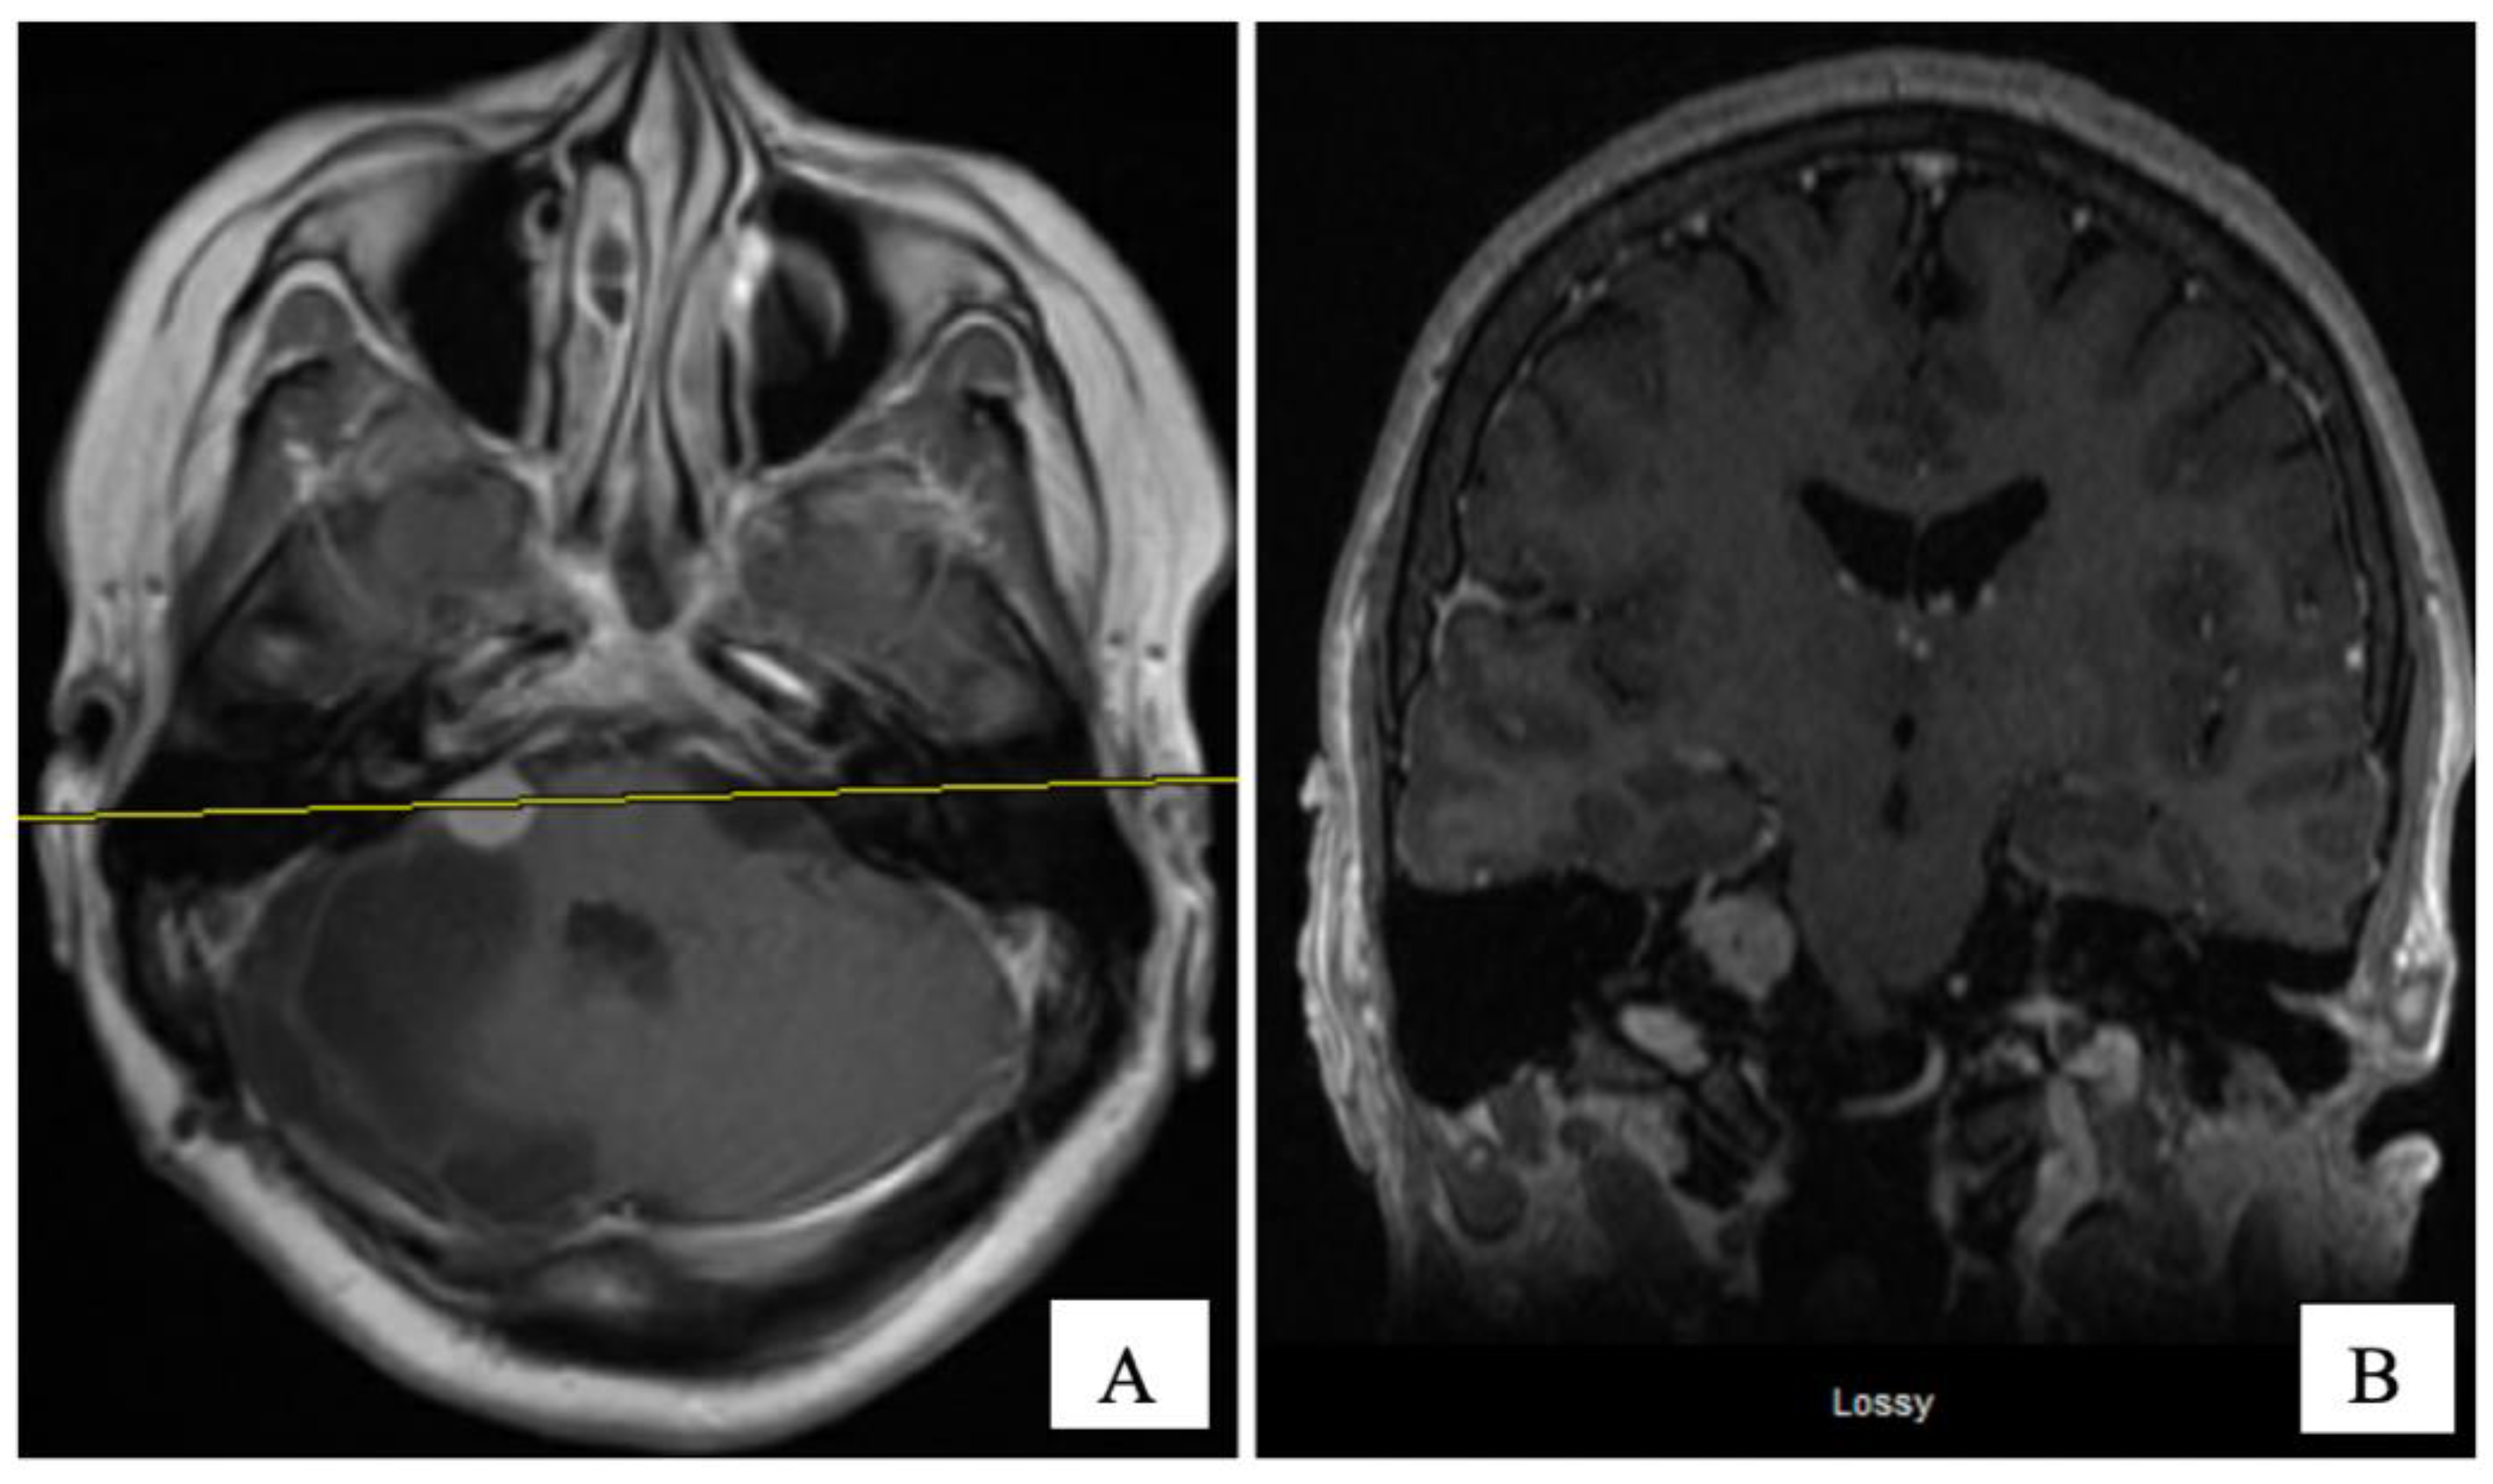

An MRI of the brain on May 2008 (Figure 2A,B) revealed an enhancing, T1-isointense and T2-hyperintense extra-axial CPA mass lesion measuring 24 × 24 × 30 mm, associated with prominent flow-voids and causing mass-effect on the lower pons and the medulla oblongata. The mass encroached on the cisternal segments of the right 7th and 8th canal nerves complex. Inferiorly, the mass extended up to the level of the foramen magnum. Our retroactive reassessment of the CT scan of the paranasal sinuses identified multiple unilaterally prominent aberrant arachnoid granulations (arachnoid pits) of the right sphenoid bone and the focal disruption of the left planum sphenoidale, contiguous to an abnormal opacification of the medial left ethmoid sinus and upper nasal cavity, in keeping the source of a CSF leak with high intracranial pressure features (Figure 1C,D). The retrospective review of the above mentioned MRI showed a very mild compensated communicating hydrocephalus (Figure 2B).

In September 2008, the patient underwent a right posterior fossa craniotomy with facial nerve monitoring. A frozen section of the tumour revealed a CPP. The tumour was extremely vascular, soft, friable, and adherent to some cranial nerves. A subtotal excision of the tumour was performed in an attempt to preserve cranial nerve function. Final pathology revealed a WHO grade 1 CPP. Histologically, the tumour tissue had a papillary structure with a fibrovascular backbone and was covered by cuboidal to low columnar cells. Postoperatively, her headache and CSF rhinorrhea stopped, but she developed new vocal cord palsy and partial right hearing loss and her ataxia continued. MRI at eight weeks postoperatively revealed encephalomalacia and an 11 × 9 mm residual enhancing tumour in the right internal auditory canal extending into the right CPA without mass effect and resolution of the hydrocephalus (Figure 2C,D). She was kept on annual clinical and radiologic follow-up for over four years, till December 2012, where her annual follow up was discontinued as she was feeling better with stable radiological residual disease.

Figure 2. Pre-operative ((A) axial, and (B) coronal) and 2 months post-operative ((C) axial, and (D) coronal) post-gadolinium T1-W MRI sequences. The CPA tumour measured 24 × 24 × 30 mm and 11 × 9 mm, respectively.